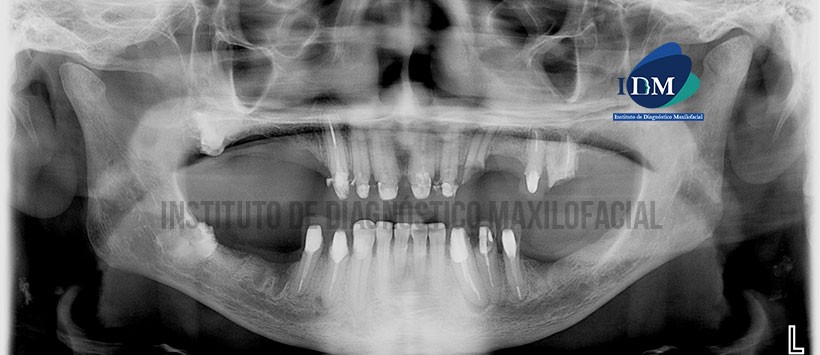

En la radiografía panorámica (Figura 1) se observa a las piezas 18 y 48 retenidas con pérdida de estructura dentaria a nivel coronario de limites definidos y forma irregular; se aprecia además resto de piezas con tratamiento protésico y tratamiento de conductos radiculares y procesos apicales en piezas 26, 33 y 44.